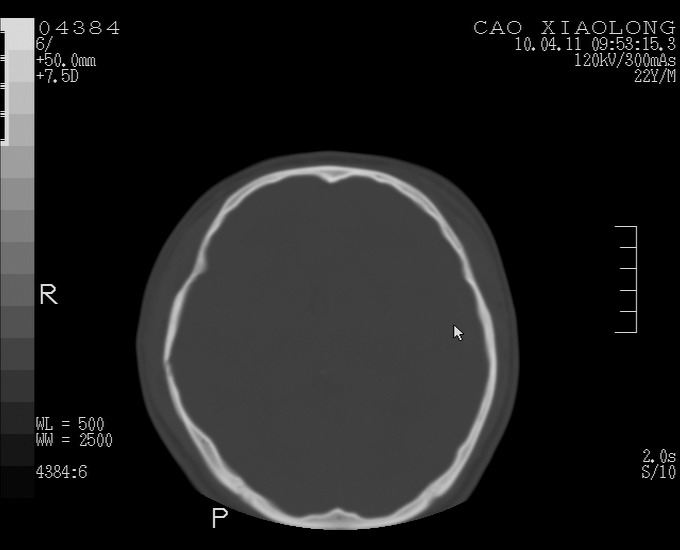

以下是引用随光逐影在2010-4-11 11:00:00的发言:[br]1)左侧额颞顶部硬膜下血肿。2)蛛网膜下腔出血。3)右侧颞顶部颅骨线形骨折。[br][br]20小时后复查:左侧额颞叶脑挫裂伤;左侧额颞顶部硬膜下血肿及蛛网膜下腔出血有吸收表现;右侧颞顶部颅骨线形骨折。[br]